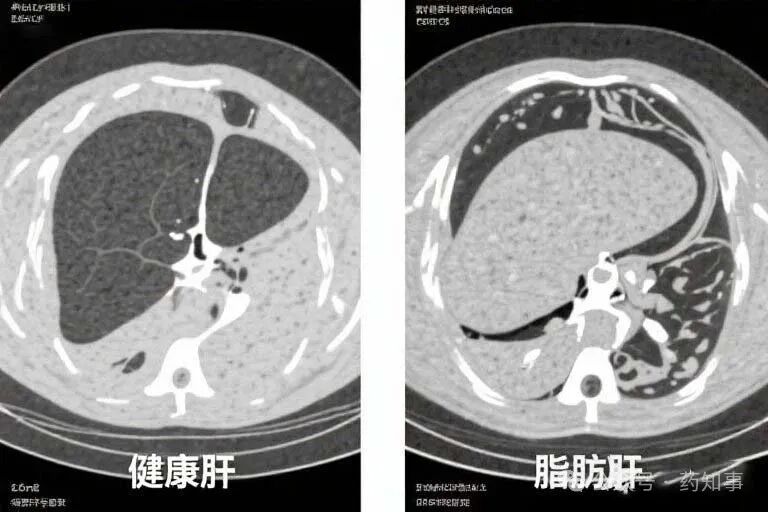

第一名:脂肪肝(每2个老爸就有1个中招)

⚠️ 危险信号(中3条就要警惕):

✓ 饭后右肋下隐隐发胀

✓ 晨起口苦有异味

✓ 啤酒肚越来越顽固

✓ 体检AST/ALT指标超30